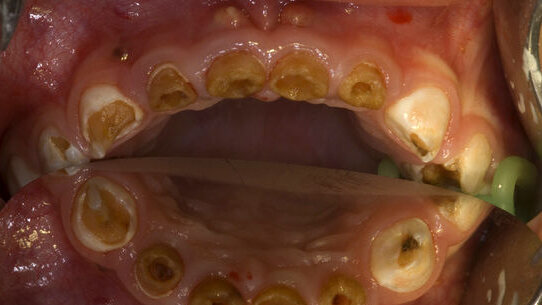

Die mit der neuen Regelleistungsvolumina verbundene drastische Honorarabsenkung hatte dazu geführt, dass insbesondere Kinderzahnärzte Probleme bekamen, Anästhesisten zu finden, für nicht kostendeckende Honorare zwischen 29 und 49 Euro kleine Patienten unter Narkose zu behandeln. Ende des Jahres 2008 hatten die Verbände erstmals Alarm geschlagen. „Das ist ein wichtiger Zwischenschritt“, sagte BuKiZPräsidentin Drs. Johanna Kant am Montag in Oldenburg. Die qualitativ gute Versorgung von Kleinkindern mit schweren kariösen Gebisszerstörungen und erblichen Zahnkrankheiten, aber auch von extrem ängstlichen und behinderten Kindern, lasse sich nun wieder planen und mittelfristig sicherstellen. Bis zu 15 Prozent der Kleinkinder in Deutschland leiden an schweren Zahnproblemen, die oftmals ohne ambulante Narkosen nicht behoben werden können. Betroffen sind ca. 70.000 Kinder pro Geburtsjahrgang.

Dennoch geben sich die Kinderzahnärzte noch nicht zufrieden. „Es ist notwendig, die Honorierung sämtlicher ambulanter Narkosen zu vereinheitlichen, damit die Anästhesisten uns Zahnärzten ausreichend Leistungen anbieten und wir unseren Sicherstellungsauftrag auch langfristig erfüllen können“, fordert Drs. Kant. Sie verweist auf aktuelle Wartezeiten von mehreren Monaten für Anästhesieleistungen in der zahnärztlichen Behandlung. „Das ist unzumutbar für unsere Patienten.In den meisten Fällen muss schnell behandelt werden, um irreparable Schäden für Gebiss und Kiefer und damit auch hohe Folgekosten für die Solidargemeinschaft zu vermeiden. Ausgerechnet Kinder und behinderte Patienten dürfen nicht die Leidtragenden des Gesundheitssparkurses sein“, betonte die BuKiZ-Präsidentin und erinnerte an die UN-Kinderrechtskonvention, Artikel 24: „Kinder haben ein Grundrecht auf das erreichbare Höchstmaß an Gesundheit sowie auf Inanspruchnahme von Einrichtungen zur Behandlung von Krankheiten und zur Wiederherstellung der Gesundheit.“